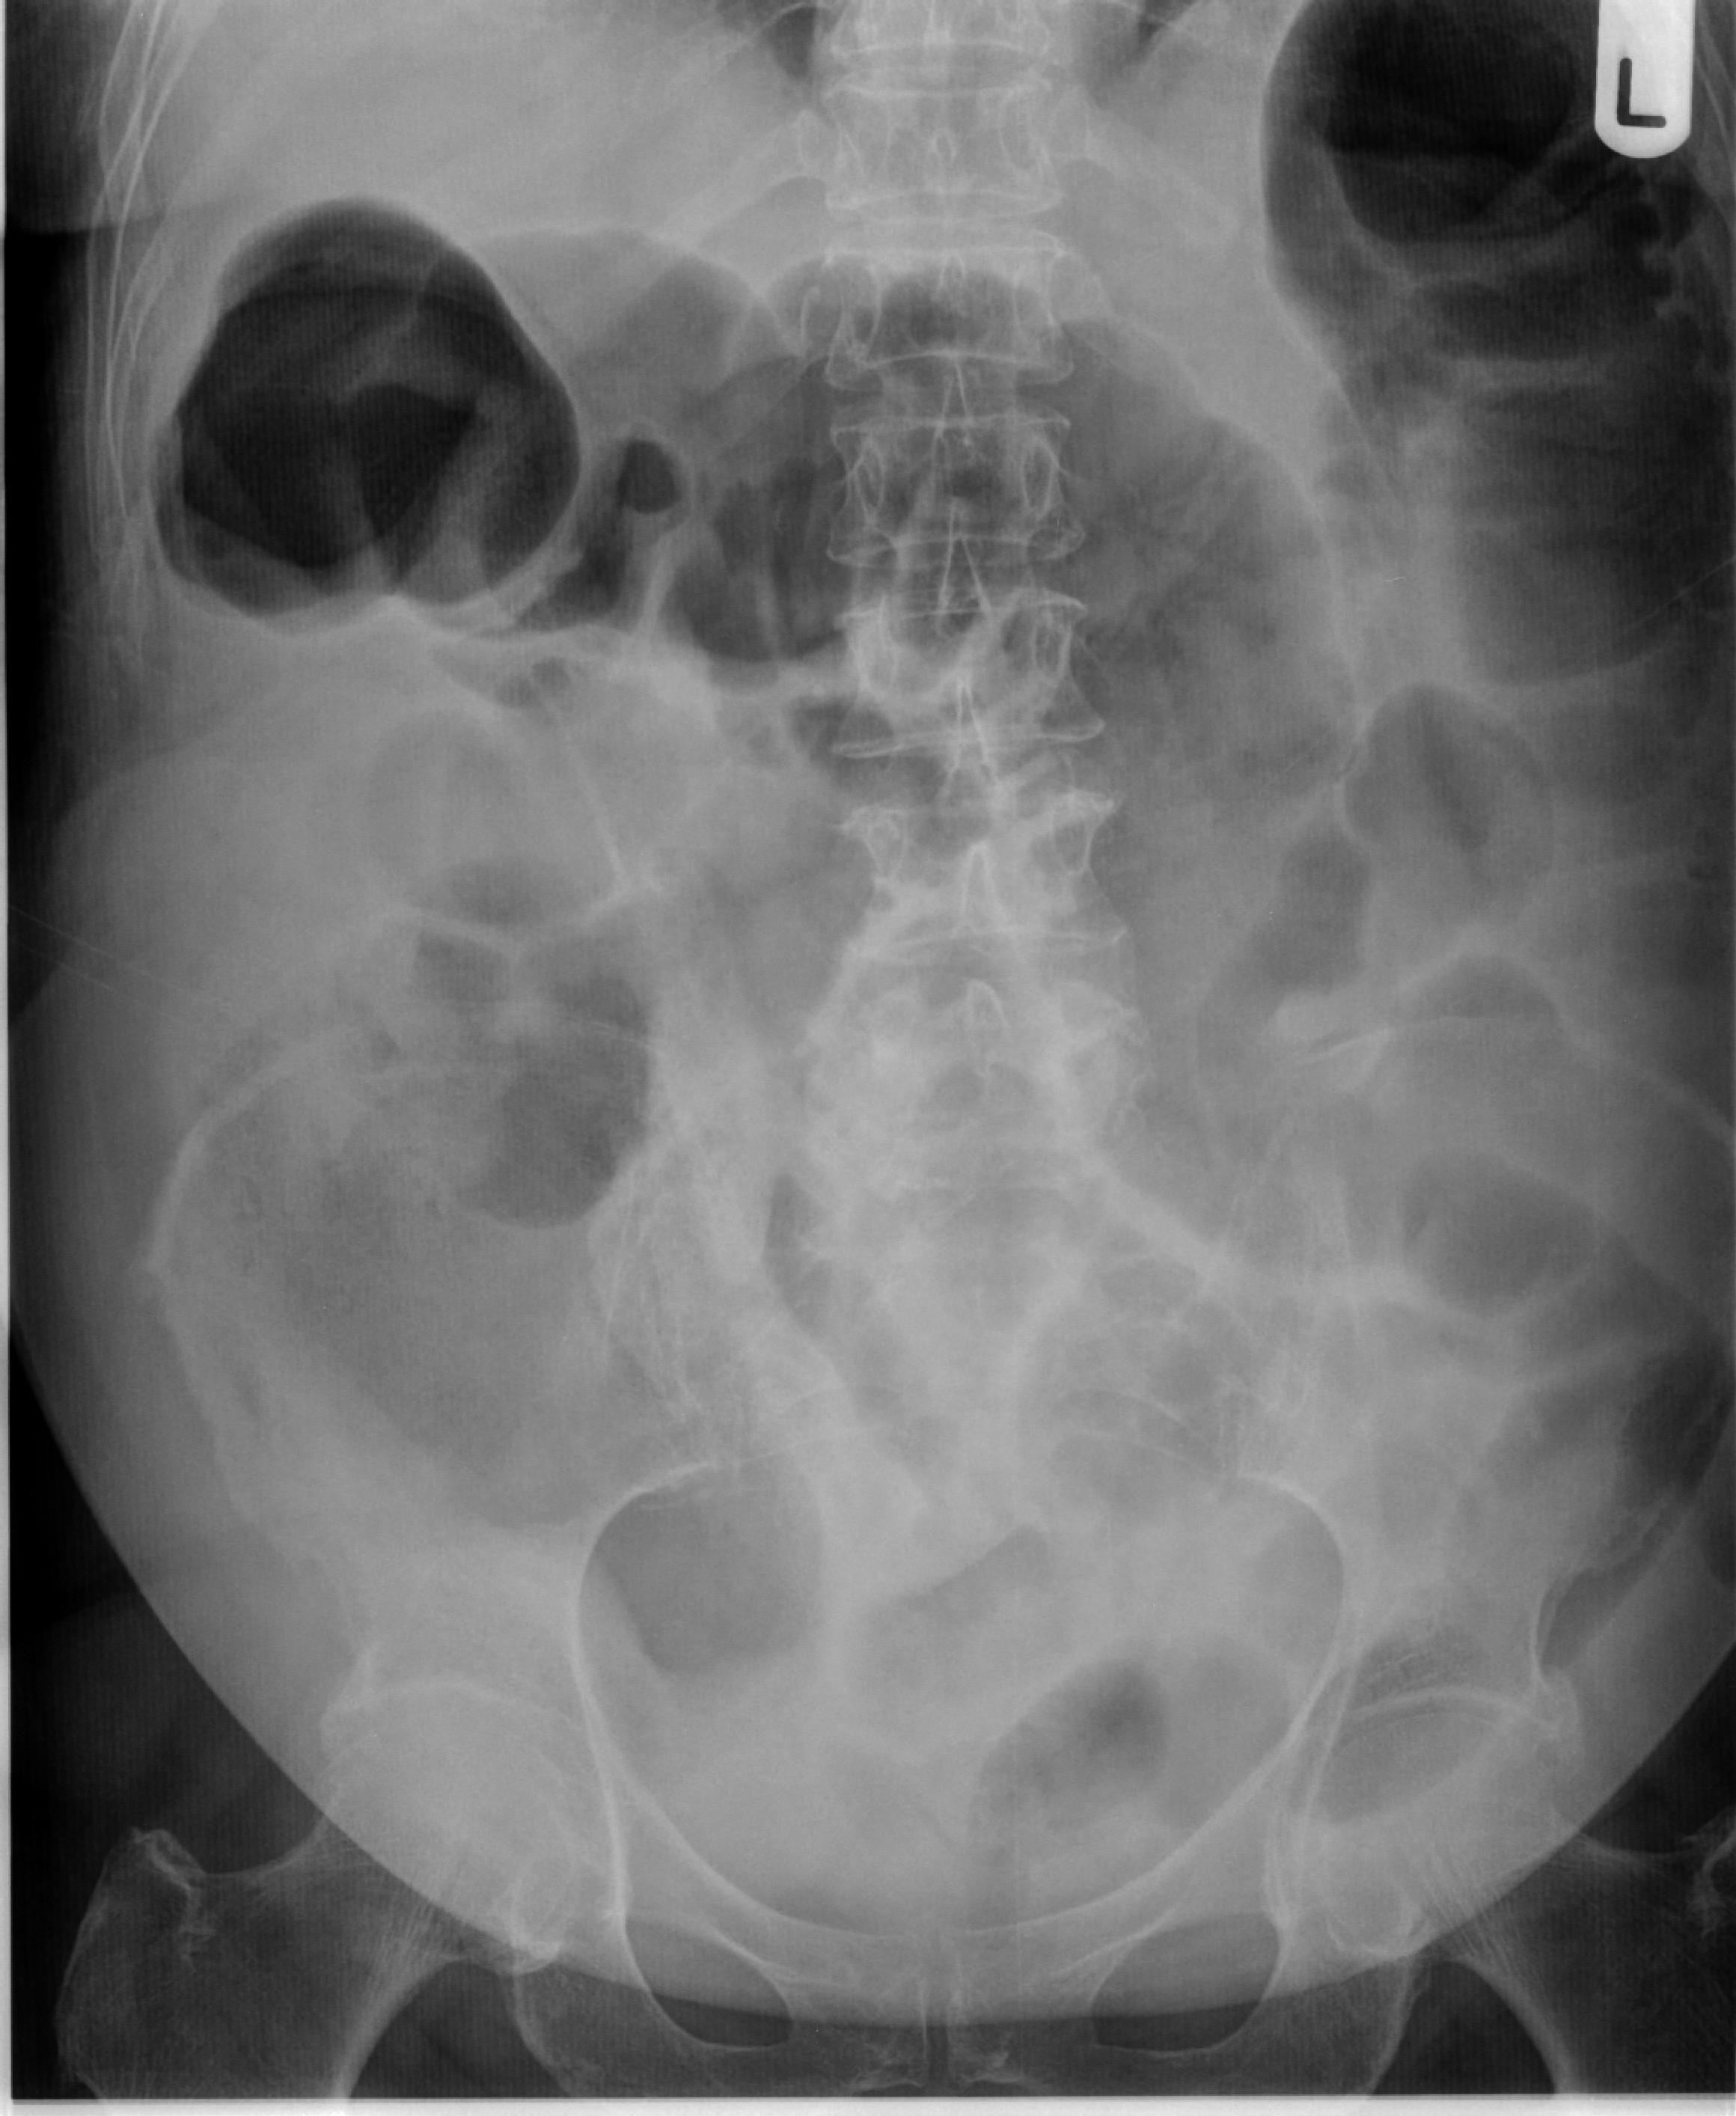

Abdominal X Ray Showing Small Bowel Obstruction Download Scientific Psyllium Intestinal Blockage It is important to instruct patients who are receiving psyllium. apart from bezoar formation, additional potential gastrointestinal side effects of psyllium use include cramps, intestinal. psyllium can worsen the constipation if not taken appropriately. intestinal obstruction can result from psyllium usage in patients who are. It works by increasing the bulk of your stool. table of. Psyllium Intestinal Blockage.

Supine view of the abdomen in a patient with intestinal obstruction Psyllium Intestinal Blockage It works by increasing the bulk of your stool. psyllium (sil i yum) may support digestion and heart health. intestinal obstruction can result from psyllium usage in patients who are. apart from bezoar formation, additional potential gastrointestinal side effects of psyllium use include cramps, intestinal. table of contents. psyllium can worsen the constipation if not. Psyllium Intestinal Blockage.